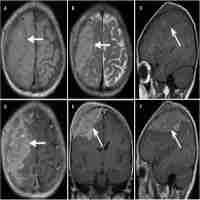

| Abstract | Background Neuroblastoma (NB) is the most common extracranial solid tumor in children. It is known for high heterogeneity and concealed onset. In recent years, the mechanism of its occurrence and development has been gradually revealed. The purpose of this study is to summarize the clinical characteristics of children with NB and abnormal chromosome 10, and to investigate the relationship between the number and structure of chromosome 10 abnormalities and NB prognosis. Methods Chromosome G-banding was used at the time of diagnosis to evaluate the genetics of chromosomes in patients with NB and track their clinical characteristics and prognosis. All participants were diagnosed with NB in the Medical Oncology Department of the Beijing Children’s Hospital from May 2015 to December 2018 and were followed up with for at least 1 year. Results Of all 150 patients with bone marrow metastases, 42 were clearly diagnosed with chromosomal abnormalities. Thirteen patients showed abnormalities in chromosome 10, and chromosome 10 was the most commonly missing chromosome. These 13 patients had higher LDH and lower OS and EFS than children with chromosomal abnormalities who did not have an abnormality in chromosome 10. Eight patients had both MYCN amplification and 1p36 deletion. Two patients had optic nerve damage and no vision, and one patient had left supraorbital metastases 5 months after treatment. Conclusions The results indicated that chromosome 10 might be a new prognostic marker for NB. MYCN amplification and 1p36 deletion may be related to chromosome 10 abnormalities in NB. Additionally, NB patients with abnormal chromosome 10 were prone to orbital metastases. |